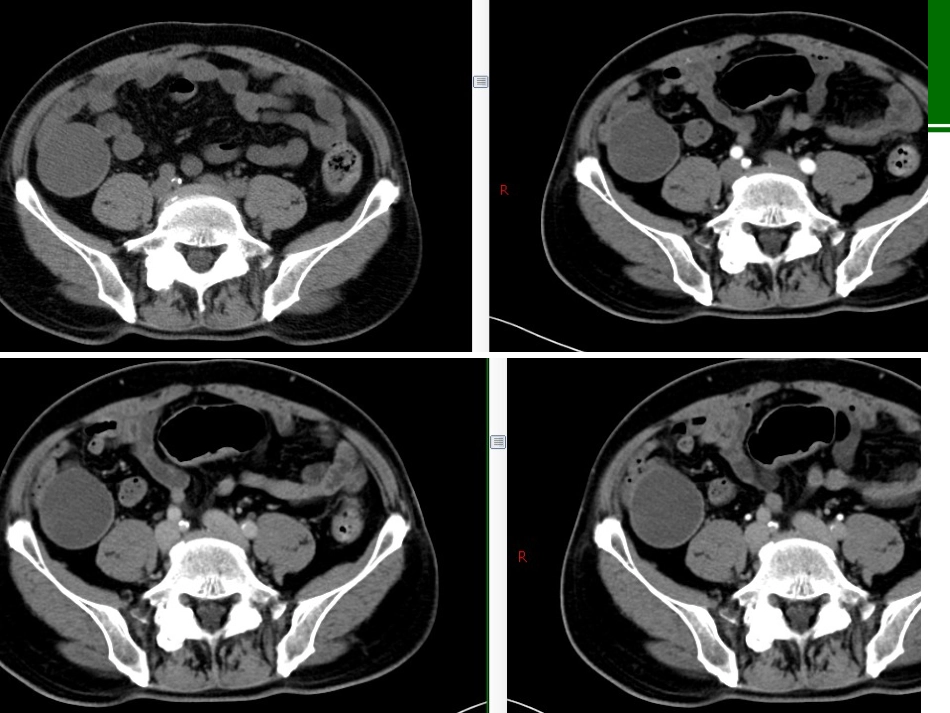

病例•男性,74岁,右下腹痛一月余,无腰背部痛及放射痛,无畏寒及发热。无肿瘤病史。•血象未见明显异常。阑尾粘液性肿瘤阑尾粘液性肿瘤:影像学表现阑尾粘液性肿瘤的典型影像学表现为:粘液囊肿。良性:阑尾黏液性囊腺瘤,粘膜层轻度异性增生、不向腔内突出、不累及肌层及浆膜层是其影像上囊壁厚薄均匀、光滑完整和均匀强化的病理基础。CT:平扫多表现为回盲部球形或类圆形囊性占位,长径小于6cm,长短径比值1.0~2.05,平均1.65;囊壁均匀菲薄,内壁较光整,囊壁可见弧形钙化,囊液密度较均匀,境界清,无分隔,少数病例周围可有少许渗出。CT增强后囊壁均匀强化,囊液无明显强化。影像学表现阑尾低级别粘液性肿瘤:位置:回盲部、右髂窝囊性占位。形态:长茄子形、不规则形、椭圆形或球形,破裂形成腹腔假黏液瘤,囊壁及钙化漂浮在黏液中。大小:长径/短径比值1.2~3.5,平均2.1。囊壁:可较均匀也可厚薄不均,多毛糙。根蒂:不均匀增厚,可见壁结节;盲肠内可见黏液。钙化:附壁蛋壳样钙化或囊内颗粒样钙化。囊内容物:密度较高,可见絮状强化。强化:囊壁轻中度强化;可出现环形强化及囊内絮状、分隔样强化。假性粘液瘤:少见。影像学表现阑尾粘液腺癌:易穿破浆膜形成腹膜假性黏液瘤及腹腔种植,少数可直接穿孔形成窦道,经窦道侵犯其他脏器;病灶粘膜向腔内突出,并可见游离实质性成分及漂浮异型细胞,并向肌层及浆膜层浸润生长是影像上囊壁厚薄不均匀,毛糙不光滑,囊液不均匀和增强后不均匀强化和条絮样强化的病理基础。肿块内实性成分更多,增强后明显强化。常伴有腹膜假性粘液瘤。鉴别诊断阑尾炎性病变:单纯阑尾炎,阑尾增粗形态存在,黏液较少,密度较低,根部可有粪石,但囊内及囊壁不会有钙化。脓肿临床表现为高热、白细胞明显增高等症状;阑尾壁水肿增厚明显,无壁结节,增强后明显环形强化,周围渗出明显。结核等炎性病变可以伴腹水,腹水密度较低,无分隔条絮样强化,无腹腔种植转移,结核冷脓肿多无钙化,与阑尾不相连。结核慢性期钙化明显,伴有淋巴结钙化、肿大及干酪样坏死;阑尾黏液性肿瘤不累及淋巴结,发现淋巴结异常支持结核或其他肿瘤。鉴别诊断阑尾黏液囊肿是指阑尾出口梗阻,导致阑尾腔扩张并黏液聚集所形成的囊性占位病变,一般阑尾根部可见粪石嵌顿而非肿瘤性软组织,病变较小,一般直径<2cm,囊壁均匀较薄光滑,一般不超过3mm,内无分隔,无壁结节,特殊染色PAS(一)。阑尾其他肿瘤多以实性为主,发生坏死囊变时,可表现为囊实性,但肿瘤实性成分比例高,且囊壁厚,囊内壁更不光整,周围可有肿大淋巴结。阑尾黏液性肿瘤主要为囊性,实性成分少,主要位于根蒂或囊壁。鉴别诊断系膜囊肿或前肠囊肿:为圆形或椭圆形等囊性包块,无明显根蒂,与系膜或肠管关系可较密切,囊壁均匀光整,囊液密度较低,结合钙化位置形态及增强后强化特点不难鉴别。(正常阑尾结构)右侧附件来源肿瘤:部分病灶定位困难总结•阑尾黏液性肿瘤分为良性的囊腺瘤、低度恶性的低级别黏液性肿瘤、恶性的黏液腺癌;黏液性肿瘤有一个从粘膜增生到瘤变再过渡为LAMN,最后癌变的逐步演变过程;•影像观察病灶部位、大小、形态、境界、根蒂和囊壁(厚度、均匀度、光滑度、完整度)、内容物(壁结节、分隔、钙化、囊液、气体)、强化(强度、均匀性、方式)、腹水、假性粘液瘤。•粘液性囊腺瘤一般局限在阑尾内,腹腔无粘液成分,囊液清、均匀,壁薄;•低级别黏液性肿瘤恶性度较低,影像表现介于黏液腺癌与囊腺瘤之间。•参考文献: